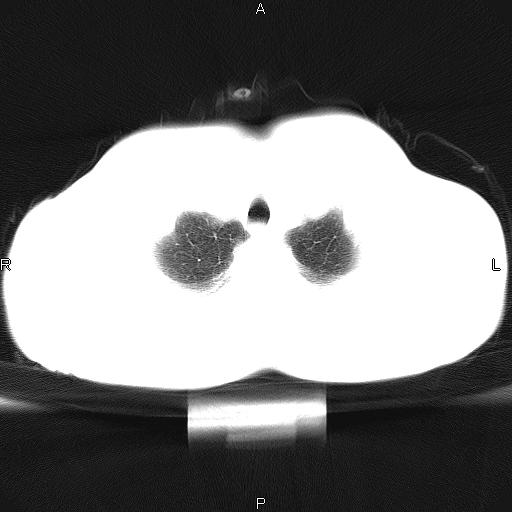

患者,男,40岁。间断发热,咳嗽二十余日。体温最高达38.9° 在当地诊所抗炎治疗三天后体温降至正常,患者自行停药。今又发热。胸片示,左下肺阴影。

左下肺片状高密度影,境界模糊,密度不均,考虑感染性病变可能性大,建议抗炎治疗后复查。左肺门增大,不除外占位性病变,必要时支气管镜检。